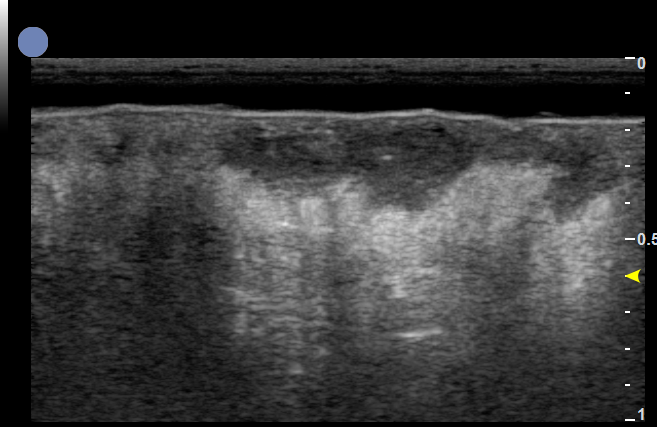

增殖期血管瘤